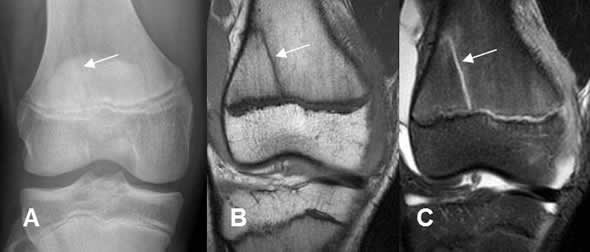

Fig 73 B. Salter tipo II.

TAC reconstrucción sagital. Fractura en la placa de crecimiento, con extensión a la metáfisis tibial.

Fig 73 C. Salter tipo II.

A: RM axial en T1, B: RM sagital en T1 y C: RM sagital en STRI. Fractura no desplazada y en sentido oblicuo, sobre la metafisis tibial, por deslizamiento epifisiario G II.